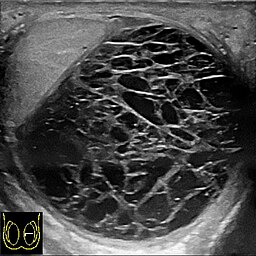

Krwiak lub obrzęk: Najczęstszą przyczyną jest krwiak, czyli nagromadzenie krwi w wyniku uszkodzenia naczyń krwionośnych podczas operacji. Może to także być obrzęk wynikający z reakcji organizmu na uraz operacyjny (to występuje z największym prawdopodobieństwem; można potwierdzić w badaniu USG; obok na zdjęciu tak wygląda krwiak w USG).